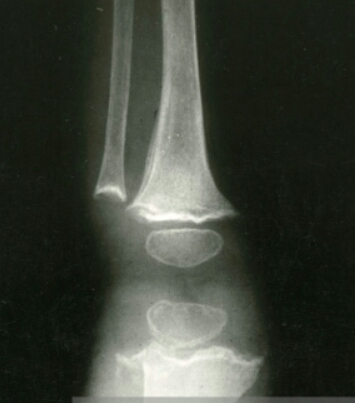

Based on this image, does this patient have an old or a new fracture?

new fracture (black is whack, white is right)

Based on this image, does this patient have a new or old fracture?

old fracture (black is whack, white is right)